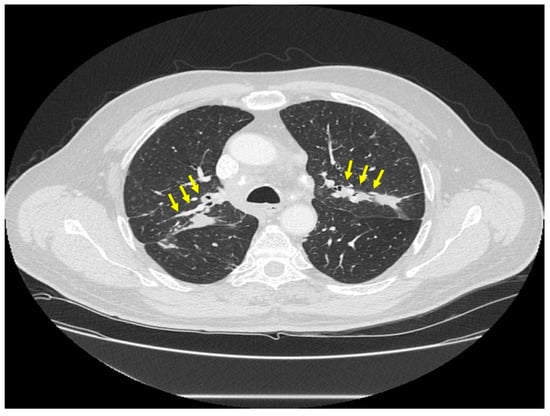

Figure 3.

Chest CT scan image of a patient with pulmonary sarcoidosis demonstrating lung opacities from granulomatous inflammation around pulmonary vessels (thin arrows). Scatter parenchymal nodules and hilar adenopathy are seen, especially on the right (thick arrow).